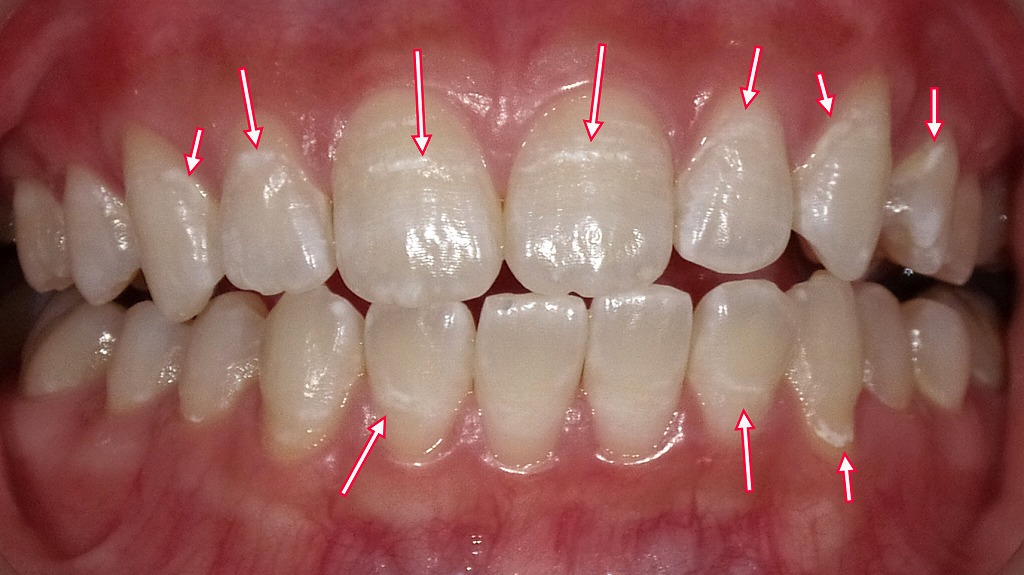

この画像は、歯の脱灰(だっかい)を示す典型的な症例です。赤い矢印で示された部分に、白く濁ったような斑点や筋状の変化が見られます。これらは、エナメル質の表面が酸によって溶けはじめた初期の虫歯(C0)や脱灰のサインです。

脱灰が進むと、歯の表面に白い斑点(ホワイトスポット)が現れます。これは虫歯のサインであり、早めに対処すれば削らずに済むケースもあります。

初期には白い斑点が出て、見た目の違和感が出ます。